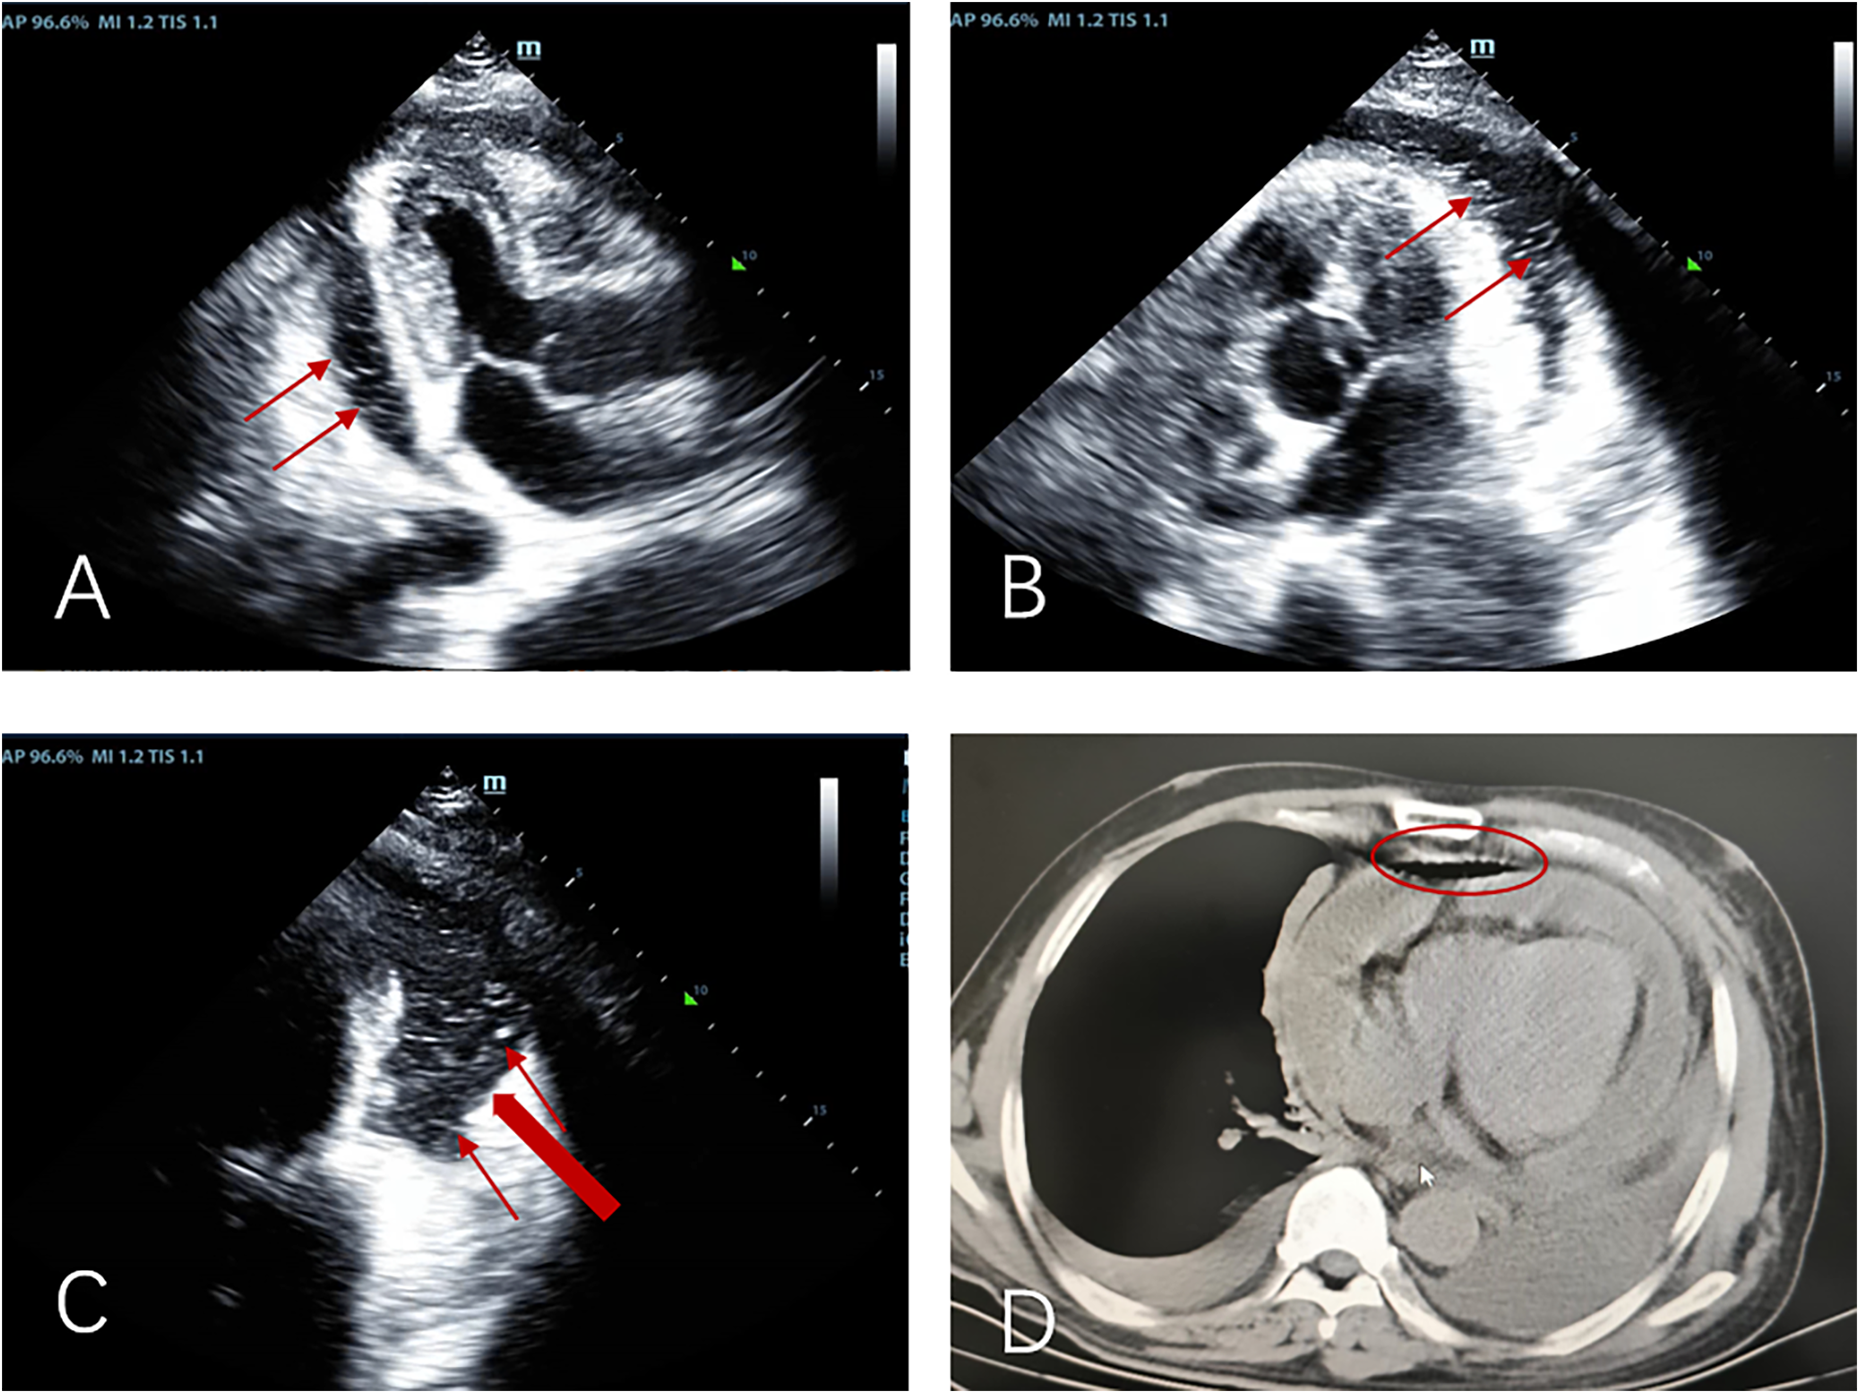

The patient's initial echocardiogram showed only minimal pericardial effusion (Figure 1A), managed expectantly. Upon admission, ultrasound revealed worsening effusion (14 mm RV anterior wall) with fibrinous strands (Figure 1B). Combined with the patient's signs of low-grade fever, pericardial friction rub and laboratory findings (white blood cell count 14.4 × 10⁹/L, neutrophil proportion 85.0%, CRP 140.9 mg/L), infectious inflammation was highly suspected clinically. Given the rapid progression of the patient's condition, to avoid delaying anti-infective treatment, blood culture or pericardial fluid culture was not performed, and an empirical anti-inflammatory regimen was initiated: anti-inflammatory treatment was administered with Cefoperazone Sodium and Tazobactam Sodium for Injection combined with 40 mg of intravenous methylprednisolone in 100 mL of normal saline. The pivotal diagnostic moment came on day 5 when echocardiography detected rotating microbubbles near the AV groove, suggesting fistulous gas entry—later confirmed by CT as pneumopericardium (Figure 2; Supplementary Movies 1–2).

Figure 2

Apical three-chamber view (A), apical five-chamber view (B), and apical four-chamber view (C) consistently demonstrate: moderate pericardial effusion with pneumopericardium, “Swirling microbubble sign” (microbubbles originating from the lateral pericardium, thin red arrow), suspected communication between pericardial space and bronchus/residual lung tissue (thick red arrow); (D) pre-decompression chest CT demonstrating gas and effusion accumulation in the pericardial cavity.

Clinical deterioration occurred abruptly on day 6 following violent coughing: the patient developed acute respiratory distress with pulsus paradoxus. Emergency echocardiography demonstrated dramatic microbubble proliferation, air gap artifacts, and a fluid-gas level (Figures 3A–C; Supplementary Movie 3), confirming tension pneumopericardium. Immediate ultrasound-guided pericardiocentesis (Figure 3D) was performed in the sitting position (2nd intercostal space): approximately 100 mL of gas was successfully drained during this procedure, after which a closed thoracic drainage system was placed for continuous pericardial drainage lasting 6 h (Figure 3E; Supplementary Movie 4).

Figure 3

The apical five-chamber view (A), non-standard apical view (B), and apical four-chamber view (C) demonstrate superior displacement of the heart with increased intrapericardial gas compared to Figure 2, showing characteristic air-gap artifacts and air-fluid levels (indicated by yellow arrows). Notably, the swirling microbubble density has increased while gas volume decreased (marked by red circles). (D) Gas was aspirated from the pericardium (indicated by the red arrow); (E) gas was drained into the negative-pressure drainage bottle; (F) a reexamination 4 h after drainage showed a significant reduction in intrapericardial gas.

Post-procedural echocardiography showed significant resolution of intrapericardial gas (Figure 3F), confirming effective decompression.